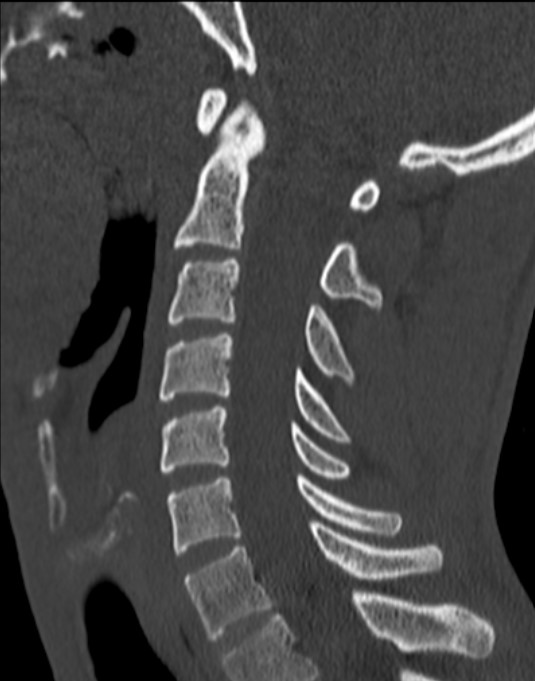

Normal Images Cervical Spine Lateral Xray Cervical Spine CT Cervical Spine MRI Sagittal Cervical Spine MRI Axial Lumbar Spine AP Xray Lumbar Spine Lateral Xray Lumbar Spine CT sagittal Lumbar Spine MRI sagittal Lumbar Spine MRI axial